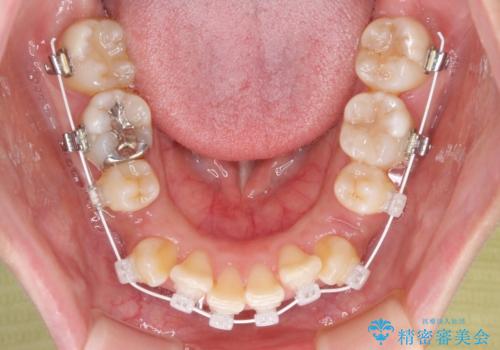

- 矯正装置

- 審美装置

- 上下前歯のデコボコを気にして来院された患者様です。

デコボコが強いため、非抜歯で矯正をすると出っ歯仕上がりとなるため、上下左右の第一小臼歯4本を抜歯することとしました。

当初予定は2年半程度と伝えていましたが、2年にも満たない期間で治療を終えることができました。